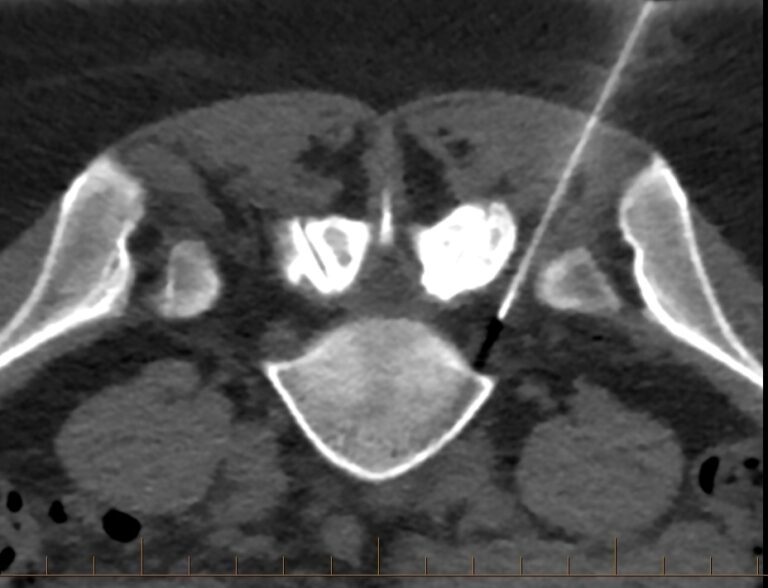

CTguided injection. Axial section showing the tip of the 22G spinal How Much Does A Ct Guided Injection Cost Near New South Wales Spinal interventional injections are one of the pain management procedures we offer. ct guided injections are used to deliver medications straight into an area (typically back and neck) that is effected by. It is an alternative treatment for. Find out about our fees,. Prp understand that knowing upfront what your. navigating through medicare and out of pocket costs. How Much Does A Ct Guided Injection Cost Near New South Wales.